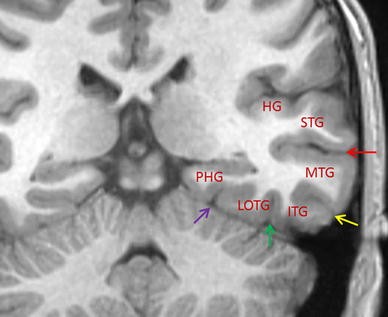

The Best 20 Temporal Lobe Axial Mri Brain Anatomy